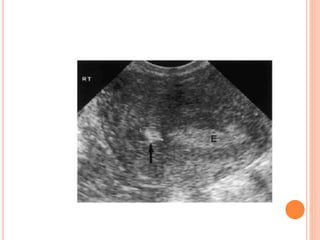

ULTRASOUND  Sonographic featuresof adenomyosis are variable and may be absent.  The reported sensitivity and specificity of trans- abdominal ultrasound are 32-63% and 95-97% respectively 7.  The spectrum of findings includes:  Normal appearing uterus  Focal or diffuse myometrial bulkiness, typically of the posterior wall .  Thickening of the transition zone can sometimes be visualised as a hypoechoic halo surrounding the endometrial layer of ≥12 mm thickness

 Subendometrial echogeniclinear striations  Subendometrial echogenic nodules (specific sign)  Small myometrial cysts / sub endometrial cysts (specific sign)  Heterogeneous echogenicity (heterogenous myometrial echotexture)  hyperechoic: islands of endometrial glands  hypoechoic: associated muscle hypertrophy  a "Venetian blind" appearance may be seen due to subendometrial echogenic linear striations and acoustic shadowing where endometrial tissues cause a hyperplastic reaction